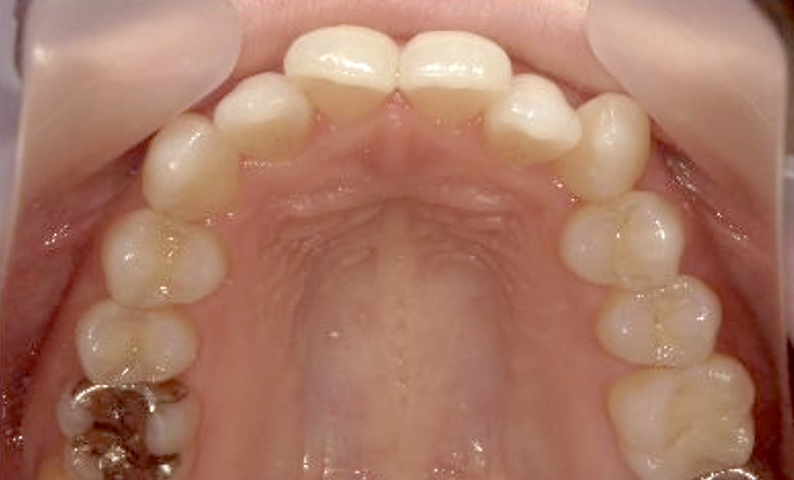

症例_018 上顎だけの部分矯正

治療期間:7ヶ月金額:30万円+税女性前歯のガタガタ上の前歯だけ

| Before | After |

|---|---|

|